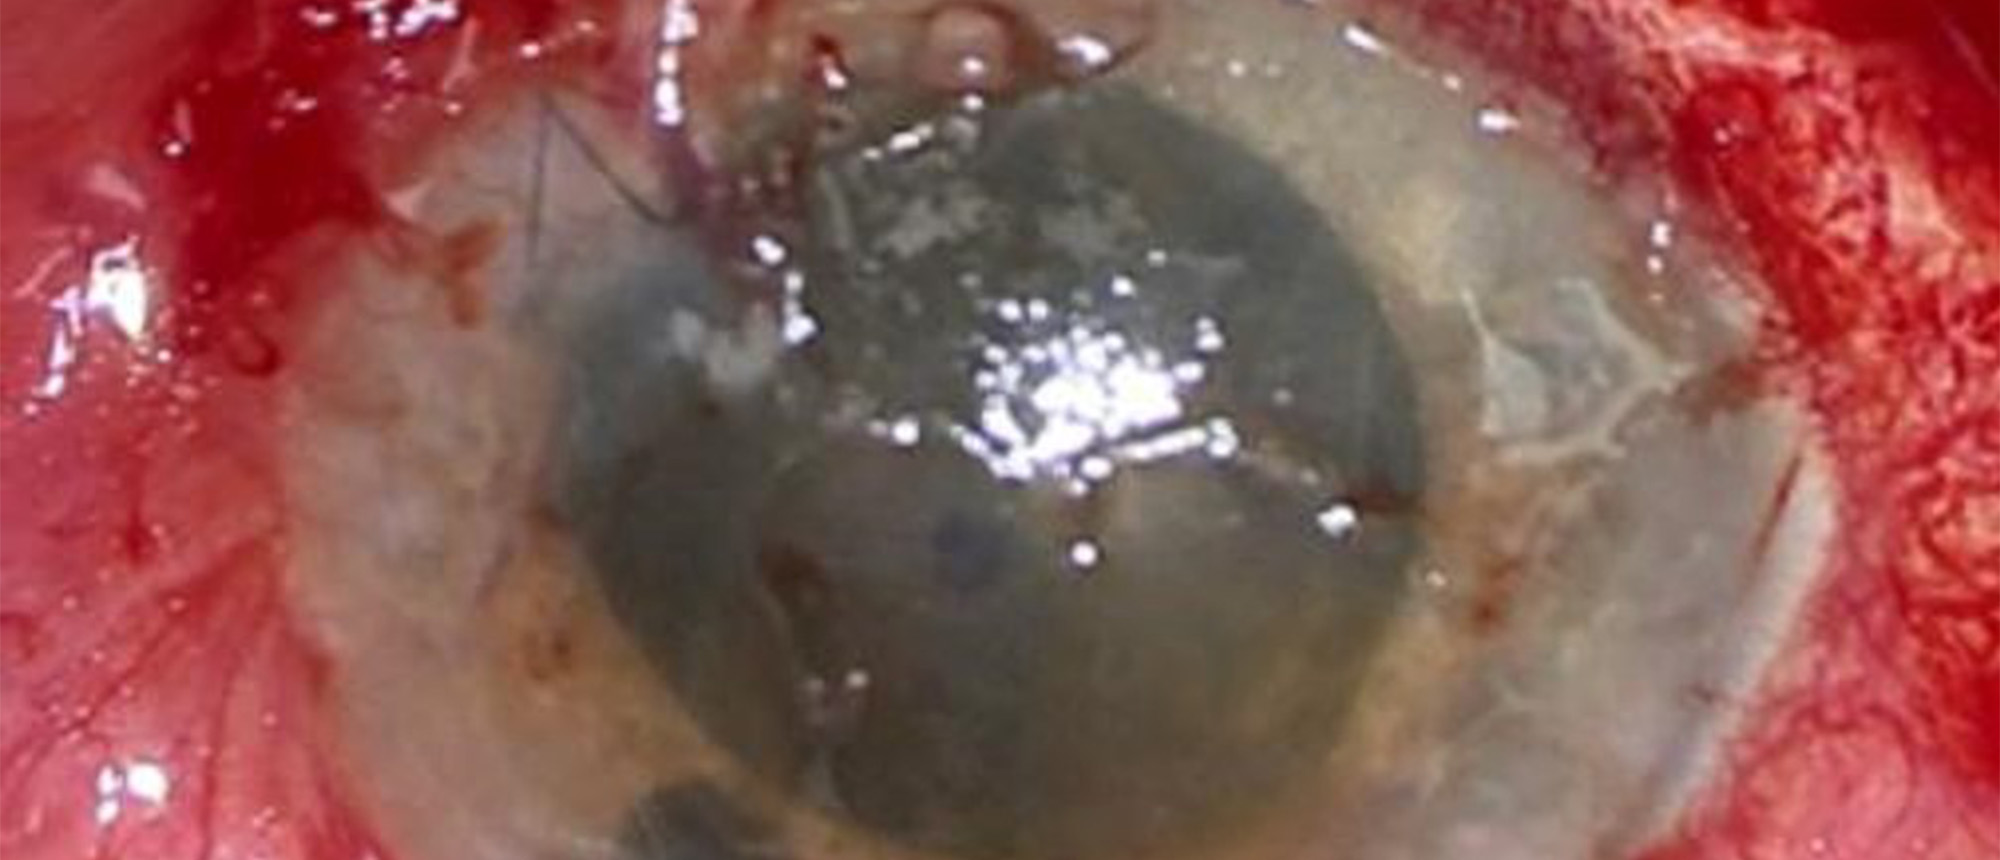

Abstract A middle-aged patient with past medical history significant for HIV (well-controlled on bictegravir, emtricitabine, and tenofovir) and history of Monkeypox infection presents to the emergency room complaining of foreign body sensation, redness, and itchiness in his right eye for two days. …

Intraocular Helminth A middle-aged patient with past medical history significant for HIV (well-controlled on bictegravir, emtricitabine, and tenofovir) and history of Monkeypox infection presents to the emergency room complaining of foreign body sensation, redness, and itchiness in his right eye fo…